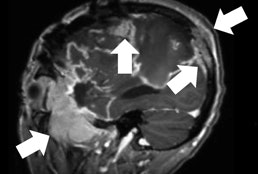

Concurrent dexamethasone limits the clinical benefit of immune checkpoint blockade in glioblastoma.

Iorgulescu JB, Gokhale PC, Speranza MC, Eschle BK, Poitras MJ, Wilkens MK, Soroko KM,... Reardon DA. (2021).

Clinical Cancer Research, 27(1), 276–87. https://doi.org/10.1158/1078-0432.CCR-20-2291